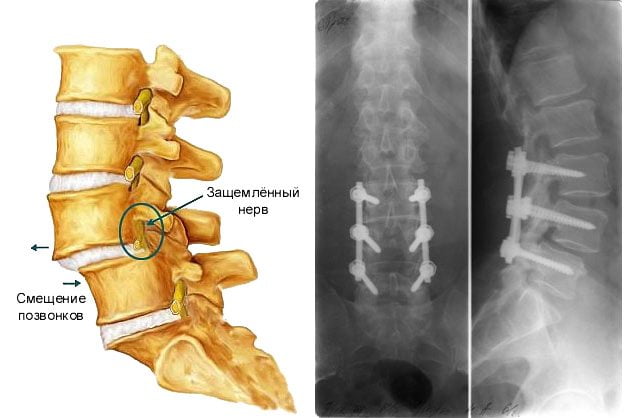

В случае нарастания клинических признаков компрессионного давления в позвоночном канале, подтвержденного комплексным диагностическим обследованием, лечащими специалистами принимается решение о хирургическом лечении.

Оперативные методы лечения имеют клинические показания:

- компрессионное давление с нарастающими признаками расстройства моторных функций, так как есть риск парализации нервной системы и нарушения функциональной работы тазобедренных костно-суставных компонентов;

- присутствие стойкого синдрома радикулоишемического характера, при котором комплексная терапия не эффективна;

- постоянное проявление рецидива компрессионно-ишемического и рефлекторно-болевого типа с выраженной нестабильностью в зоне сегментарного поражения;

Основная задача нейрохирургической операции заключается в создании декомпрессионных условий репозицией (сопоставлением) смещенного сегмента позвоночной оси, его стабилизации.